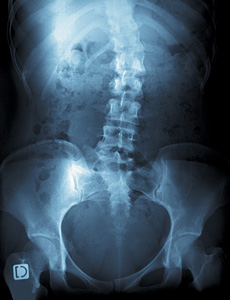

According to the Mayo Clinic, "Scoliosis is a sideways curvature of the spine that occurs most often during the growth spurt just before puberty. While scoliosis can be caused by conditions such as cerebral palsy and muscular dystrophy, the cause of most scoliosis is unknown. Most cases of scoliosis are mild, but severe scoliosis can be disabling. An especially severe spinal curve can reduce the amount of space within the chest, making it difficult for the lungs to function properly. Children who have mild scoliosis are monitored closely, usually with X-rays, to see if the curve is getting worse. In many cases, no treatment is necessary. Some children will need to wear a brace to stop the curve from worsening. Others may need surgery to straighten severe cases of scoliosis."1

Three-dimensional lateral curvatures of the spine affect 2-3 percent of the adolescent population.2 Utilizing 2000 U.S. Census Bureau statistics, the number of adolescents in the United States is 41,747,962. If 2.5 percent of all adolescents have scoliosis based on the 2-3 percent estimate, this equates to 1,043,699 (1.04 million) children facing issues as a result of scoliosis.3 Yet keep in mind that "only 10% of adolescents diagnosed with scoliosis have curve progression requiring medical intervention."4

Lou, et al., state: "Brace (orthotic) treatment is recommended for growing children with curves of 25-45 [degrees] Cobb angle. Surgery is the final treatment option for curves greater than 45° and its goals are to obtain safe correction, to produce a solid spinal fusion of the curve region, and to bring the spine and body into a more balanced position."2 However, they conclude, "Although brace treatment for scoliosis has been used for more than fifty years, its effectiveness is still debatable. ... Most studies used the amount of curve progression (as measured by the Cobb angle) to determine the effectiveness of brace treatment. Some defined success as 5° or less curve progression."2